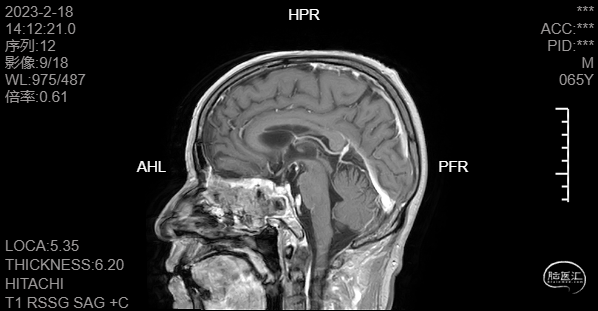

头颅磁共振T2冠矢状位平扫提示积液主要位于蝶窦腔内,筛窦及上颌窦相对干净,且未见明显占位征像。

术后MR增强复查